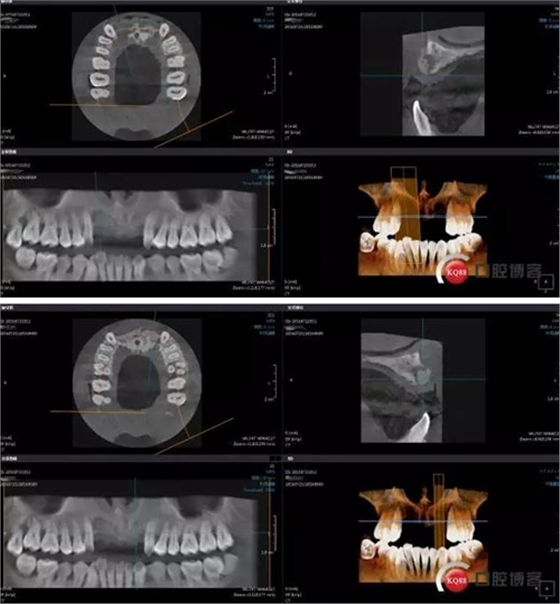

接下來(lái)是GBR五個(gè)月后CBCT,當(dāng)然(1-5月)中間也有拍全景,不一一展示了。

成骨效果尚可,進(jìn)行手術(shù)